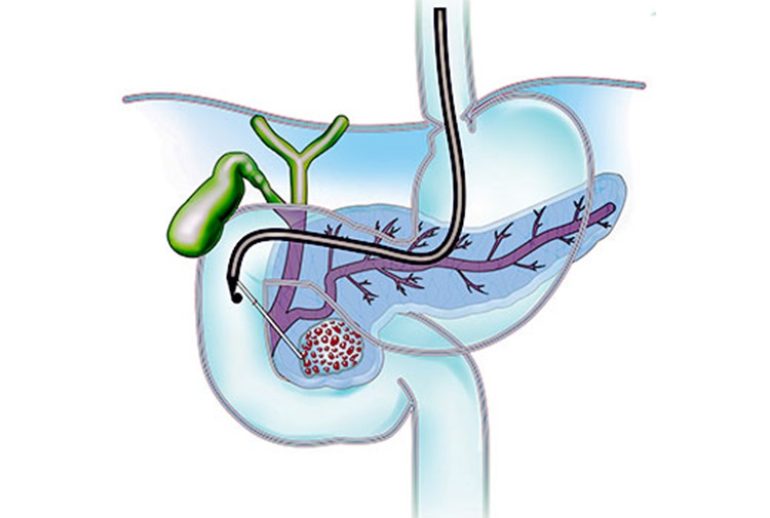

- اندوسونوگرافی: این روش ترکیبی از آندوسکوپی و سونوگرافی است و میتواند تصاویر دقیقتری از کیست ارائه دهد.

- تخلیه از طریق آندوسکوپی: در این روش، پزشک با استفاده از یک لوله نازک و دوربیندار (آندوسکوپ) کیست را تخلیه میکند. این روش کمتهاجمی است و معمولاً نیاز به بستری شدن طولانی مدت ندارد.